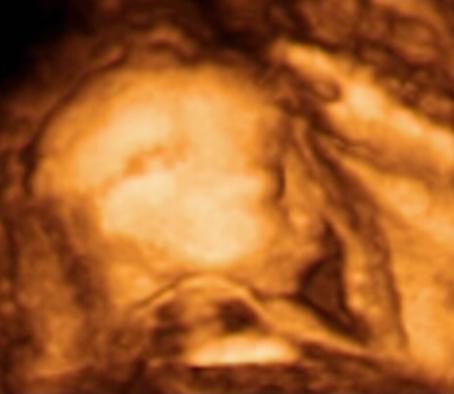

babetko sa krasne hybe